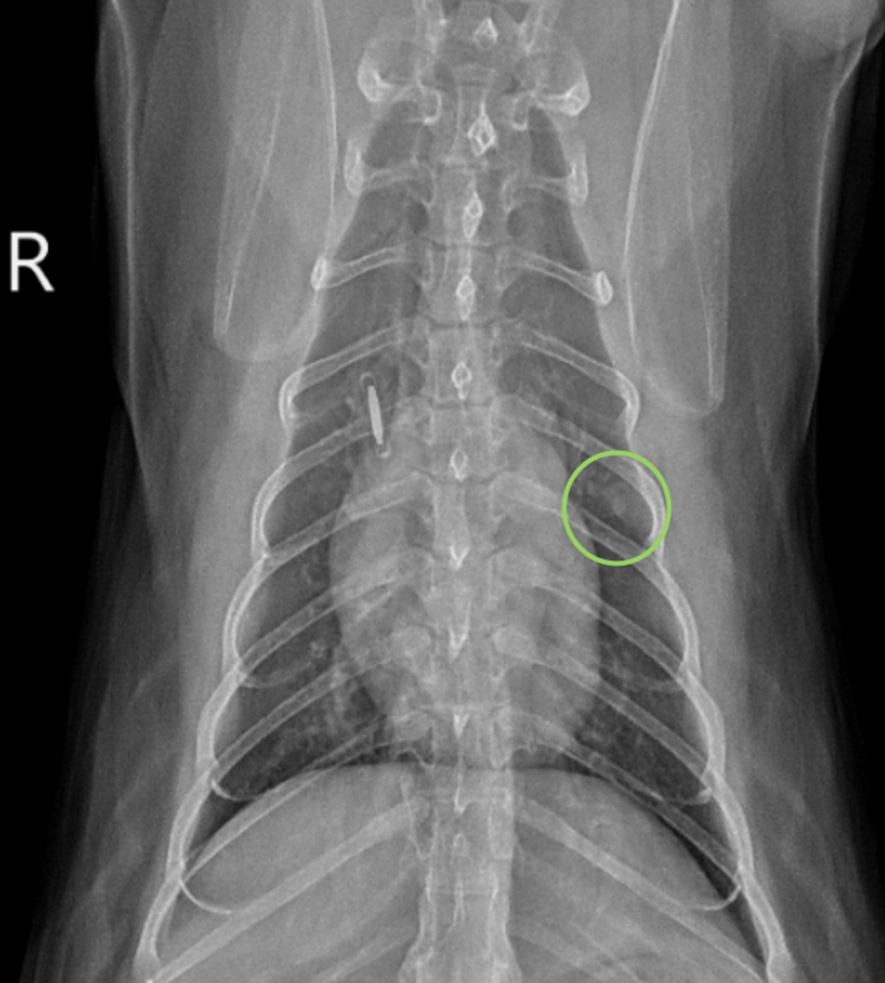

A 12-year-old male neutered domestic short hair presented for general screening prior to undergoing general anesthesia for an annual dental cleaning, and to re-evaluate a small soft tissue to mineral opaque pulmonary nodule noted in the left 5th intercostal space on thoracic radiographs obtained 5 months prior (encircled in green on the ventrodorsal view below). Differentials for the nodule included a granuloma, osteoma, or, less likely, neoplasia (metastatic vs early primary). The patient has a history of occasional vomiting secondary to presumptive chronic enteropathy and/or chronic pancreatitis, equivocal nonprogressive heart disease based on previous echocardiograms, and rare episodes of coughing. A grade II/VI left systolic heart murmur and mild periodontal disease were identified on physical exam.